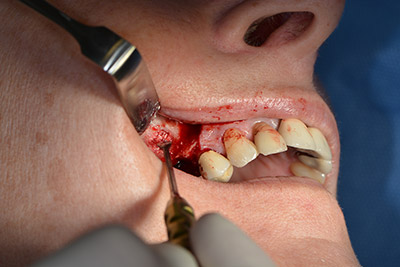

El guiado clásico del corte (crestal, descarga bucal) y la preparación del colgajo mucoperióstico permiten obtener una buena visión global.

En este caso se utilizan implantes Sky (Bredent), cuyo protocolo quirúrgico exige el fresado piloto a unas 1.200 rpm (figura 9).